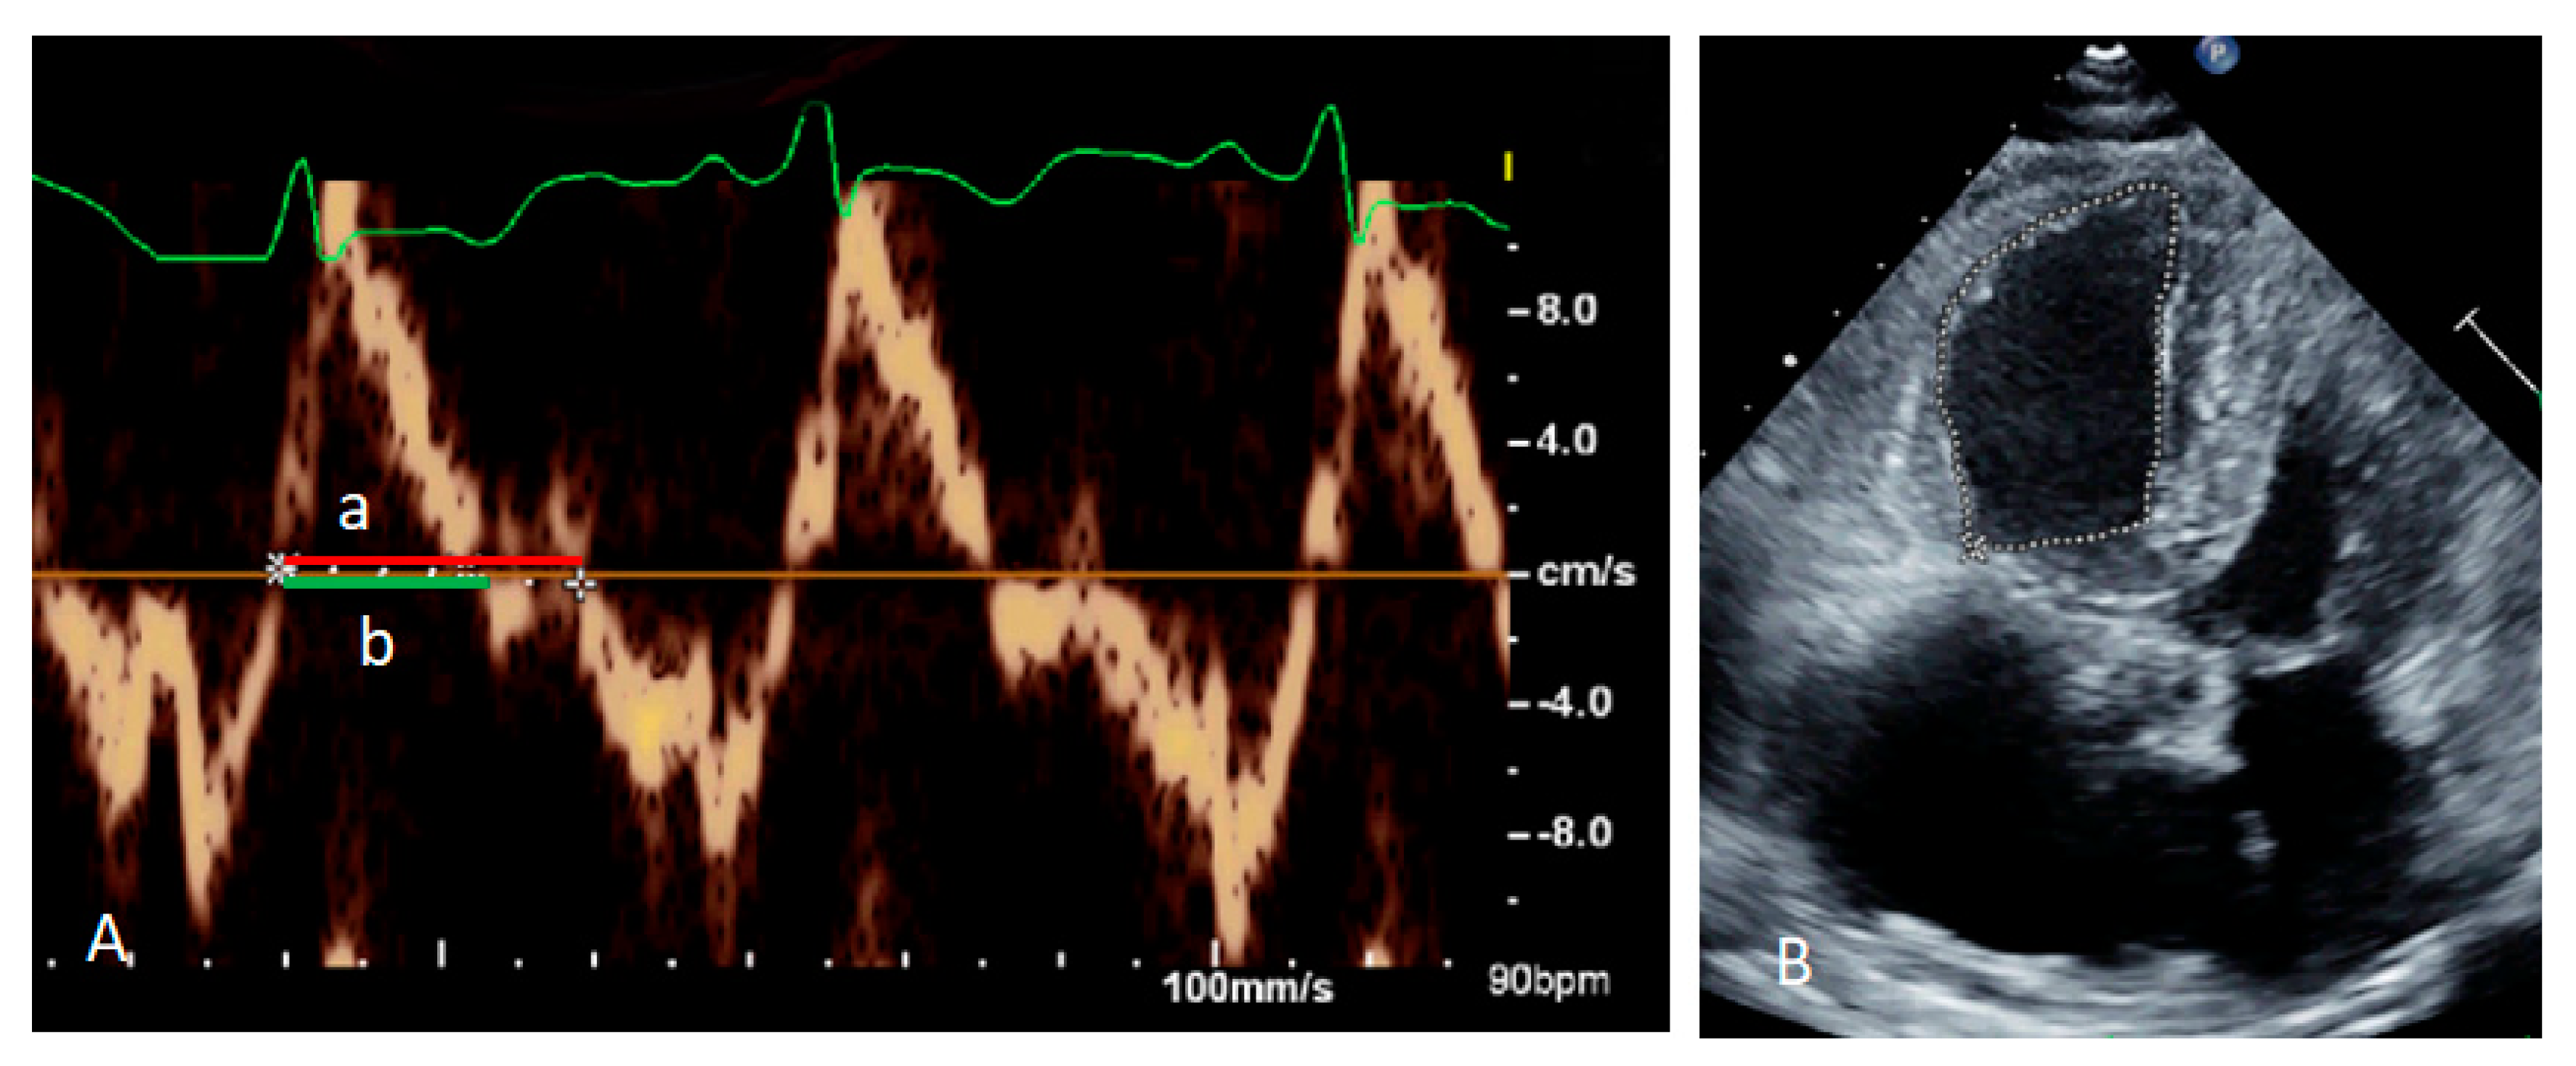

| Left ventricular ejection fraction | 59.7% |

| Systolic pulmonary artery pressure | 96 mmHg |

| Right ventricle size | 31 mm |

| RV index of myocardial performance | 0.64 |

| RV fractional area change | 21% |